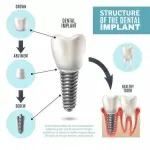

У меня есть небольшое воспаление в зоне сопряжения верхушки корня переднего зуба с клыком. Врач предложил трехчасовую операцию под седацией, удаление клыка и установка 6-и имплантов (4 сверху, 2 снизу). У меня есть аллергия на металлы, но доктор заверил, что аллергии на титан быть не может.

Пять дней назад мне установили 1 имплант по моей просьбе, как индикатор аллергии. Болей нет, но есть ощущения батарейки за щекой, в зоне установки импланта кислый, пощипывающий привкус.

Проведение одномоментной имплантации и удаления допустимо, но, рекомендуем Вам обратиться к аллергологу и проверить состояние на наличие аллергии. Как правило, аллергическая реакция отсутствует, но всегда может быть риск. Рекомендуем Вам посетить аллерголога.